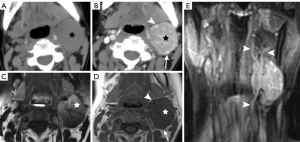

Due to its location between the vein and artery in the carotid space, schwannomas of the vagus nerve tend to separate the artery and vein, usually displacing the CCA/ICA medially and the IJV laterally (Figures 2,3) (12). Some schwannomas of the vagus nerve may displace the IJV and ICA/CCA in a posterior direction without splaying them and there is usually separation between the artery and vein (Figure 4). The cervical sympathetic chain runs in a fascial reflection posterior and slightly medial to the carotid space. Hence, schwannomas of the sympathetic chain tend to displace the IJV and CCA/ICA together, usually anteriorly and laterally (Figure 5) (5). A large schwannoma of the sympathetic chain may distort the surrounding anatomy and result in a posterior displacement of the carotid vessels without separation of the artery and vein (Figure 6) (13,14). Occasionally, a schwannoma of the cervical sympathetic chain may splay the internal and external carotid arteries at the carotid bifurcation but without encasing the arteries (Figure 7) (5). In these regards, the position of the tumor relating to the vessels in the carotid space is more important than the direction of vascular displacement. There has also been a reported case of schwannoma arising from the glossopharyngeal nerve in the carotid space causing posterior displacement of the ICA (15).

Neurofibroma in the carotid space may be sporadic or a part of neurofibromatosis. Computed tomography (CT) or magnetic resonance imaging (MRI) findings of neurofibromas are often similar to those of schwannomas (Figure 8). Localized lesions typically manifest as masses that grow in a longitudinal and fusiform manner along the affected nerve (5). These masses exhibit tapered ends, indicating the parent nerve entering and exiting the tumor (16,17). A “target sign” appearance has also been described, referring to the central hypointense region of the lesion on a MRI T2-weighted imaging (T2WI) image (18).